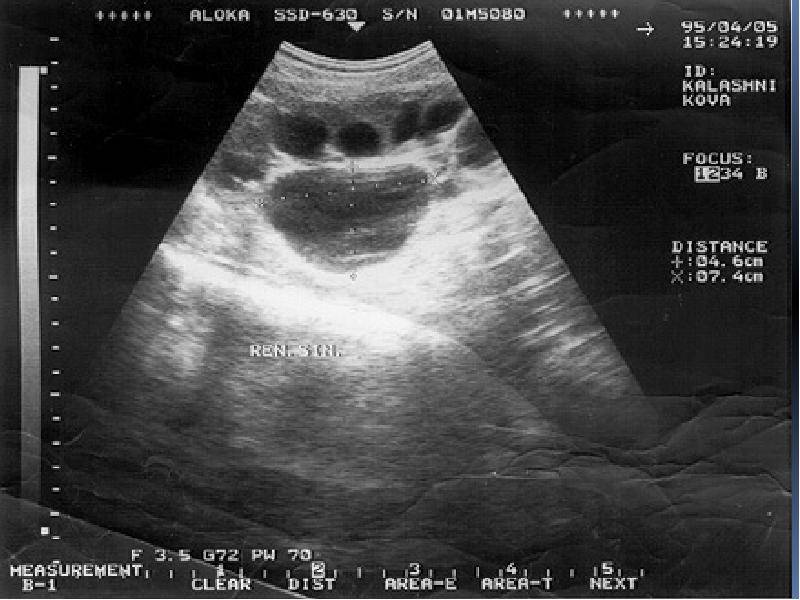

Интраренальная лоханка: рентгеновские снимки и примеры